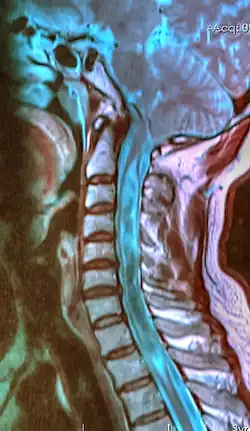

A sagittal FLAIR MRI scan, from a patient with an Arnold–Chiari malformation, demonstrating tonsillar herniation of 7 mm.

Diagnosis is made through a combination of patient history, neurological examination, and medical imaging.[27][28] Magnetic resonance imaging (MRI) is considered the preferred imaging modality for Chiari malformation.[29] The MRI visualizes neural tissue such as the cerebellar tonsils and spinal cord as well as bone and other soft tissues. CT and CT myelography are other options and were used prior to the advent of MRI, unfortunately the resolution of CT based modalities do not characterize syringomyelia and other neural abnormalities as well.[30]

By convention, the cerebellar tonsil position is measured relative to the basion-opisthion line, using sagittal T1 MRI images or sagittal CT images.[31] The selected cutoff distance for abnormal tonsil position is somewhat arbitrary, as not every person will be symptomatic at a certain amount of tonsil displacement, and the probability of symptoms and syrinx increases with greater displacement; however, greater than 5 mm is the most frequently cited cutoff number, though some consider 3–5 mm to be "borderline"; pathological signs and syrinx may occur beyond that distance.[31][32][33] One study showed little difference in cerebellar tonsil position between standard recumbent MRI and upright MRI for patients without a history of whiplash injury.[25] Neuroradiological investigation is used to rule out any intracranial condition that could be responsible for tonsillar herniation first. Neuroradiological diagnostics evaluate the severity of crowding of the neural structures within the posterior cranial fossa and their pressure against the foramen magnum. Chiari 1.5 is a term used when both brainstem and tonsillar herniation through the foramen magnum are present.[34]